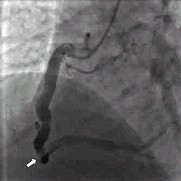

例1,男,47岁,以阵发性心前区疼痛半月入院。大量吸烟史25年,高血压病史5年。查体:心率85次/分,血压150/90mmHg,心尖区可闻及Ⅱ级收缩期杂音。血CHOL5.25mmol/L,TG3.36mmol/L。心脏彩超:左心房内径40mm,左心室舒张末期内径55mm,下壁节段性运动减弱。心电图:Ⅱ、Ⅲ、aVF导联可见病理性Q波,T波倒置。入院后行冠状动脉造影示:三支冠状动脉严重扩张;左前降支(LAD)左回旋支(LCX)前向血流TIMIⅢ级(图1);右冠状动脉(RCA)血流TIMIⅡ级,第二段与第三段反折处可见血栓影(图2)。行冠状动脉内超声(IVUS)示: 三支冠状动脉显著扩张,未见明显动脉粥样硬化斑块,RCA第二段与第三段反折处可见血栓。给予抗凝、抗血小板、转换酶抑制剂、他汀类降脂药物及硝酸酯类药物治疗,患者胸痛症状消失。随访半年,无胸痛症状发生。

图1:例1冠状动脉造影显示前降支和回旋支显著扩张